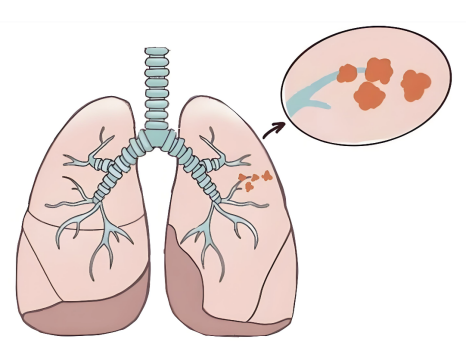

七旬肺癌晚期患者辗转求医无果 南郊医院肿瘤科精准介入治疗让生命重燃希望

七旬张大爷(化名)与肺恶性肿瘤缠斗已两年有余。自2023年10月起,他反复咳嗽、咳血伴胸闷憋喘,辗转多家医院治疗却收效甚微,病情持续加重至连进食都成难题。